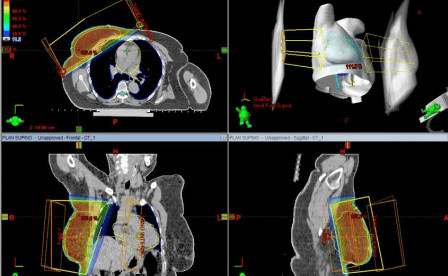

Esta técnica se basa en complejos sistemas informáticos de cálculo. La 3DCRT mejora la distribución espacial de la radiación ya que se adapta al volumen y forma del tumor mediante el uso de tomografías del paciente asociado a programas computarizados (TPS) y a la conformación del haz de radiación a través un Colimador Multiláminas (MLC).

Se puede así reproducir una imagen tridimensional fiel del tumor y los órganos vecinos de modo que el campo de radiación tenga el contorno exacto del área de tratamiento, logrando optimizar la dosis de radiación sobre la zona a tratar con protección del tejido sano, asegurándose la óptima cobertura del tumor, cualquiera sea su forma.

La 3D-CRT ha demostrado mejorar los resultados del tratamiento, comparado con la radioterapia convencional, en tumores de cerebro, cabeza y cuello, pulmón e hígado, entre otros.